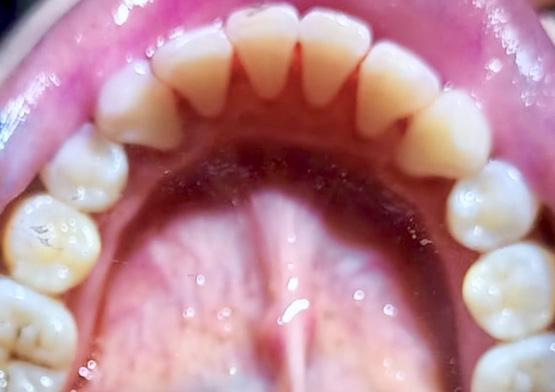

Gigi yang tidak terawat, selain bisa timbul penyakit juga menyebabkan mulut tidak sedap. Itu pasti akan sangat mengganggu keseharian kamu. Apalagi hingga munculnya karang gigi karena plak yang dibiarkan membuat tampilan gigi tampak tidak terawat. Pasalnya, plak yang mengeras cenderung berwarna kusam, bisa berwarna kuning kecokelatan hingga hitam.

Plak dan karang gigi mengandung jutaan bakteri dan jika tidak dibersihkan secara rutin, dapat menyebabkan periodontitis, kerusakan gigi, atau bahkan hilangnya gigi. Plak dan karang gigi sulit dihilangkan dengan penyikatan biasa, sehingga membutuhkan tindakan dan alat khusus melalui prosedur scaling. Selain untuk membersihkan plak dan karang gigi, scaling gigi juga bermanfaat untuk: